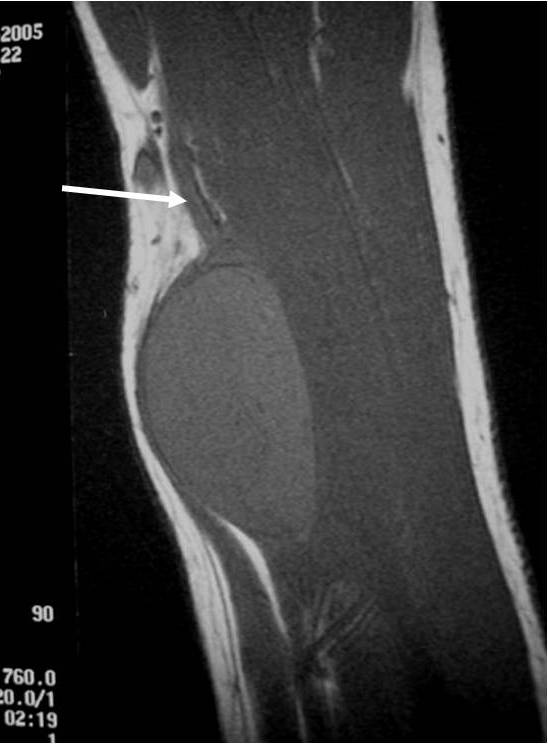

• Nerve: Tubular structure visualized entering and exiting the mass (may be difficult to see with small lesions or lesions of the trunk or retroperitoneum) (Fig. 2 & 4)

Fig. 1-4 MR image demonstrates a 5 cm intermuscular mass in the anterior compartment of the arm arising along the course of the neurovascular structures. Isointense to muscle on T1W image and heterogeneous high signal on T2W with low signal in the central area (Antoni A) and peripheral high signal (Antoni B), known as “Target Sign”. Coronal image shows a structure entering and exiting the mass (median nerve).